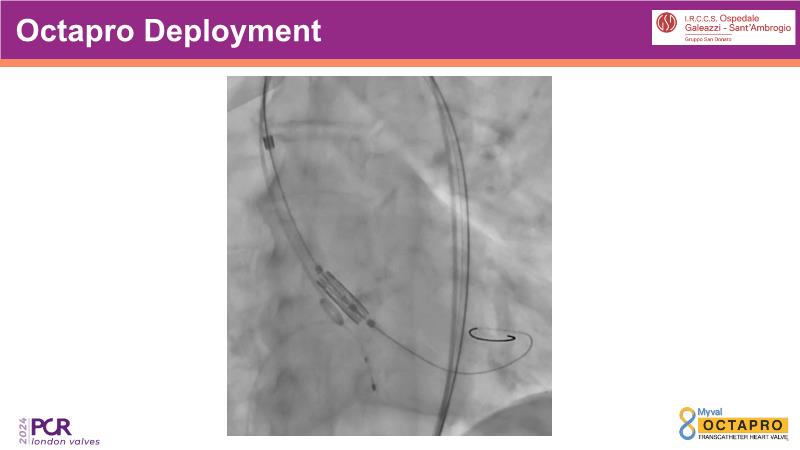

Through the presentation of several compelling cases, including an 88-year-old male with CKD, RBBB, moderate LV dysfunction, and severe aortic stenosis, a Type 1a bicuspid native AS, and an extraordinary TAVI in an 83-year-old with acute heart failure and comorbidities, this session will dive into the Myval Octapro THV. Learn about its key features, procedural impact, and potential clinical benefits. Discover the Octalign technique for predictable and precise commissural and coronary alignment, preserving coronary access. Gain insights into precise sizing, positioning, and deployment of the Myval THV series in real-world scenarios, and explore the relevance of pivotal Landmark RCTs in clinical practice.

- To learn about the novel Myval Octapro THV - Key features, the procedural impact and potential clinical benefits.

- To know the Octalign technique which enables predictable and precise commissural and coronary alignment thus preserving coronary access

- To understand the technique of precise sizing, positioning and deployment of Myval THV series in real world clinical scenarios